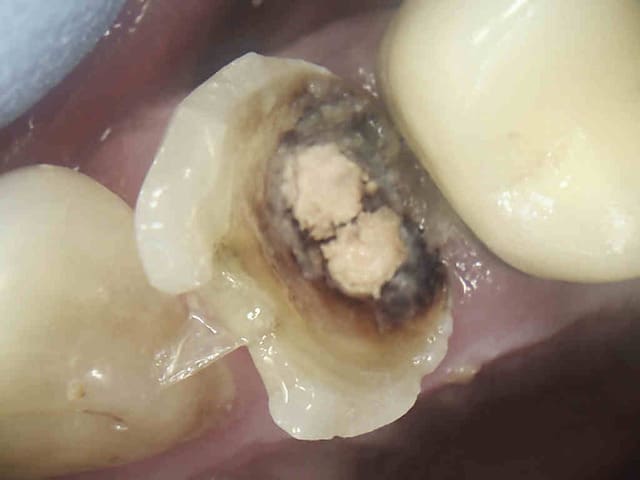

4 wgbx1x - Eugenol

3 b4nxvh - Eugenol

1 phwbbp - Eugenol